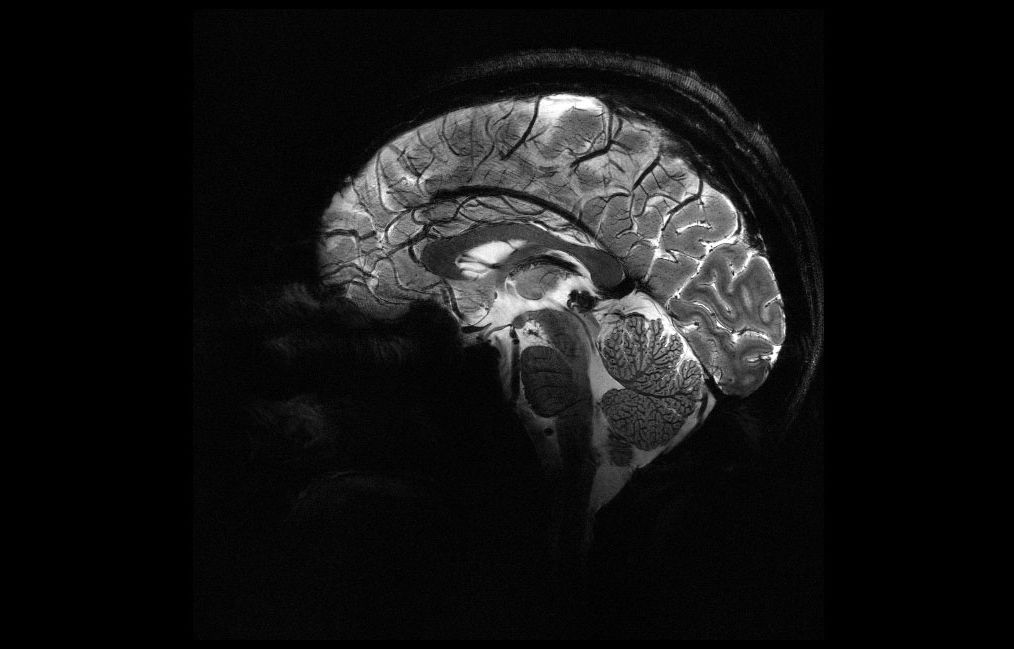

Vous avez peut-être vu les images de ce cerveau humain diffusées par les chercheurs du commissariat à l'énergie atomique et aux énergies alternatives ...

Des chercheurs français du Centre d'études CEA Paris-Saclay ont dévoilé les résultats révolutionnaires du scanner IRM Iseult, l'appareil d'IRM le plus ...

Ce ne sont, rien de moins, que les images les plus précises du cerveau humain jamais réalisées à ce jour ! Ces clichés, historiques, ont été obtenus par ...

Le CEA (Commissariat à l'énergie atomique et aux énergies alternatives) a dévoilé ce mardi 2 avril les premières images de l'IRM Iseult. Bien plus ...

Le Commissariat à l'énergie atomique et aux énergies alternatives a dévoilé ce mardi 2 avril les premières images de l'IRM Iseult, le plus puissant du ...

Cette nouvelle IRM, baptisée Iseult, a révélé des images d'une précision étonnante. Même si l'outil n'est pas encore utilisable dans les hôpitaux, les ...

L'événement était attendu depuis presque 20 ans : Iseult, l'IRM le plus puissant du monde grâce à l'intensité record de son champ magnétique, a livré ...

Ce sont les images les plus précises du cerveau humain, et surtout celles qui ont été obtenues le plus rapidement avec de degré de détail. L'imagerie ...

L'IRM le plus puissant du monde a livré, près de Paris, ses premières images du cerveau humain et est désormais prêt à mieux comprendre son fonctionnement ...

Mis au point au terme de plus de vingt ans de recherches, le super IRM du CEA, Iseult, est doté d'un champ magnétique de 11,7 teslas, contre 3 teslas maximum ...